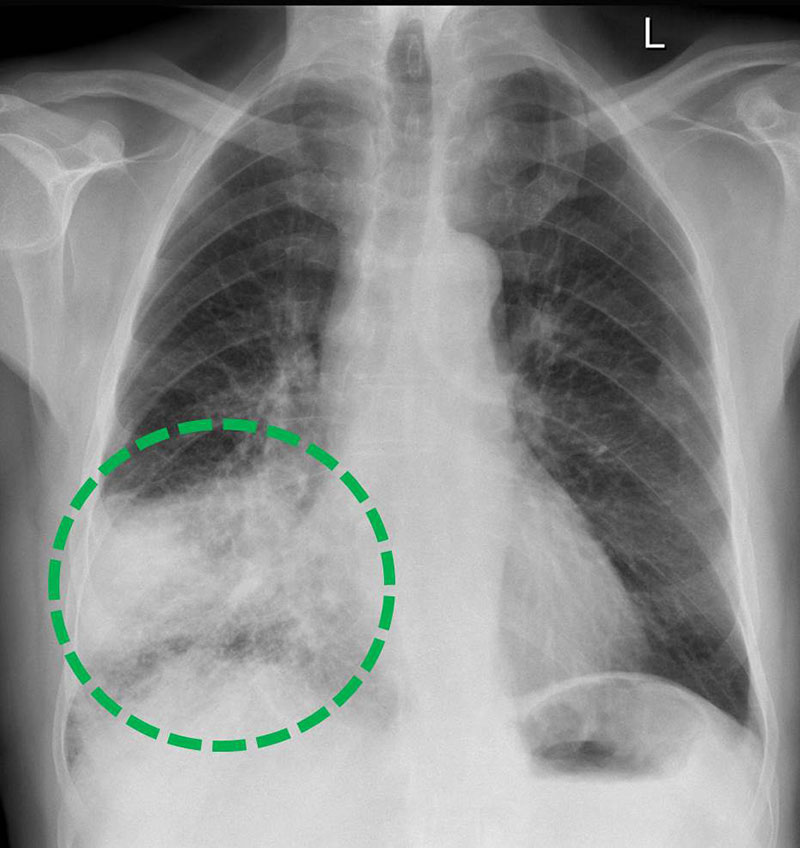

1. Übersichts-Radiographie ("Röntgen-Thorax")

Die Röntgentechnik hat die Lungendiagnostik von mehr als 100 Jahre revolutioniert. Sie bot als erste Technik einen Blick hinter die Kulissen der Thoraxwand. Bis heute ist der „Röntgen-Thorax“ die radiologische Basisdiagnostik: für die Lungenentzündung, zum Nachweis einer Wassereinlagerung bei Herzfunktionsstörungen oder zum Ausschluss bösartiger Erkrankungen. In ihrer modernsten Form mit digitaler Aufnahmetechnik und computerisierter Bildnachverarbeitung kommt die Röntgendiagnostik der Lunge an allen unseren Standorten zur Anwendung.

Röntgen-Thorax

Röntgenaufnahme einer Lungenentzündung

(Zum Vergrößern bitte anklicken)